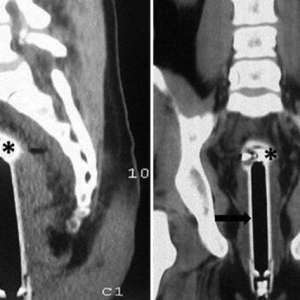

В Сомали женщина получила огнестрельное ранение клитора. Пуля была успешно извлечена с применением местной анестезии.

Согласно имеющейся информации, инцидент произошел в гостиничном номере. Двадцатичетырехлетняя потерпевшая утверждает, что во время ее пребывания в комнате кто-то произвел выстрел, пробив потолок, и пуля попала непосредственно в область ее гениталий. Напуганная случившимся, женщина немедленно обратилась за медицинской помощью. Рентгеновское обследование подтвердило наличие свинцовой пули.

Хирурги провели операцию по извлечению инородного тела, используя местную анестезию. Подчеркивается, что это уникальный случай проникающего ранения вульвы с застреванием пули в клиторе.